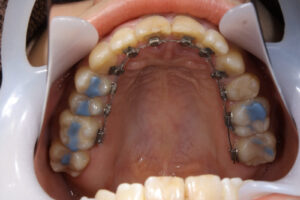

Invisalign wire orthodontics half-lingual

half-lingual

Invisalign wire orthodontics

wire orthodontics half-lingual

ワイヤー矯正で全体の歯が噛んでいる